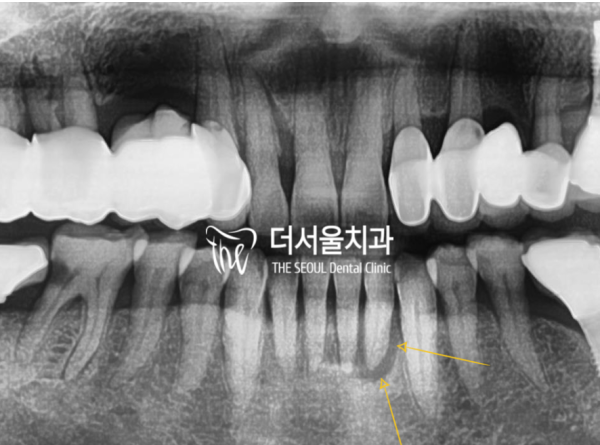

조금 더 해상도를 높인 엑스레이 사진을 보면

골 소실의 범위도 정확히 확인할 수 있습니다.

치근단 염증 위주로 넓게 퍼져있는것을 볼 수 있습니다.

이러한 상태면 치아가 흔들릴 수 밖에 없고

통증도 상당한 정도입니다.

If you look at the X-ray with a higher resolution

The extent of bone loss can also be accurately identified.

You can see that it's spread around the root of the tooth.

In this condition, your teeth will shake

The pain is also considerable.